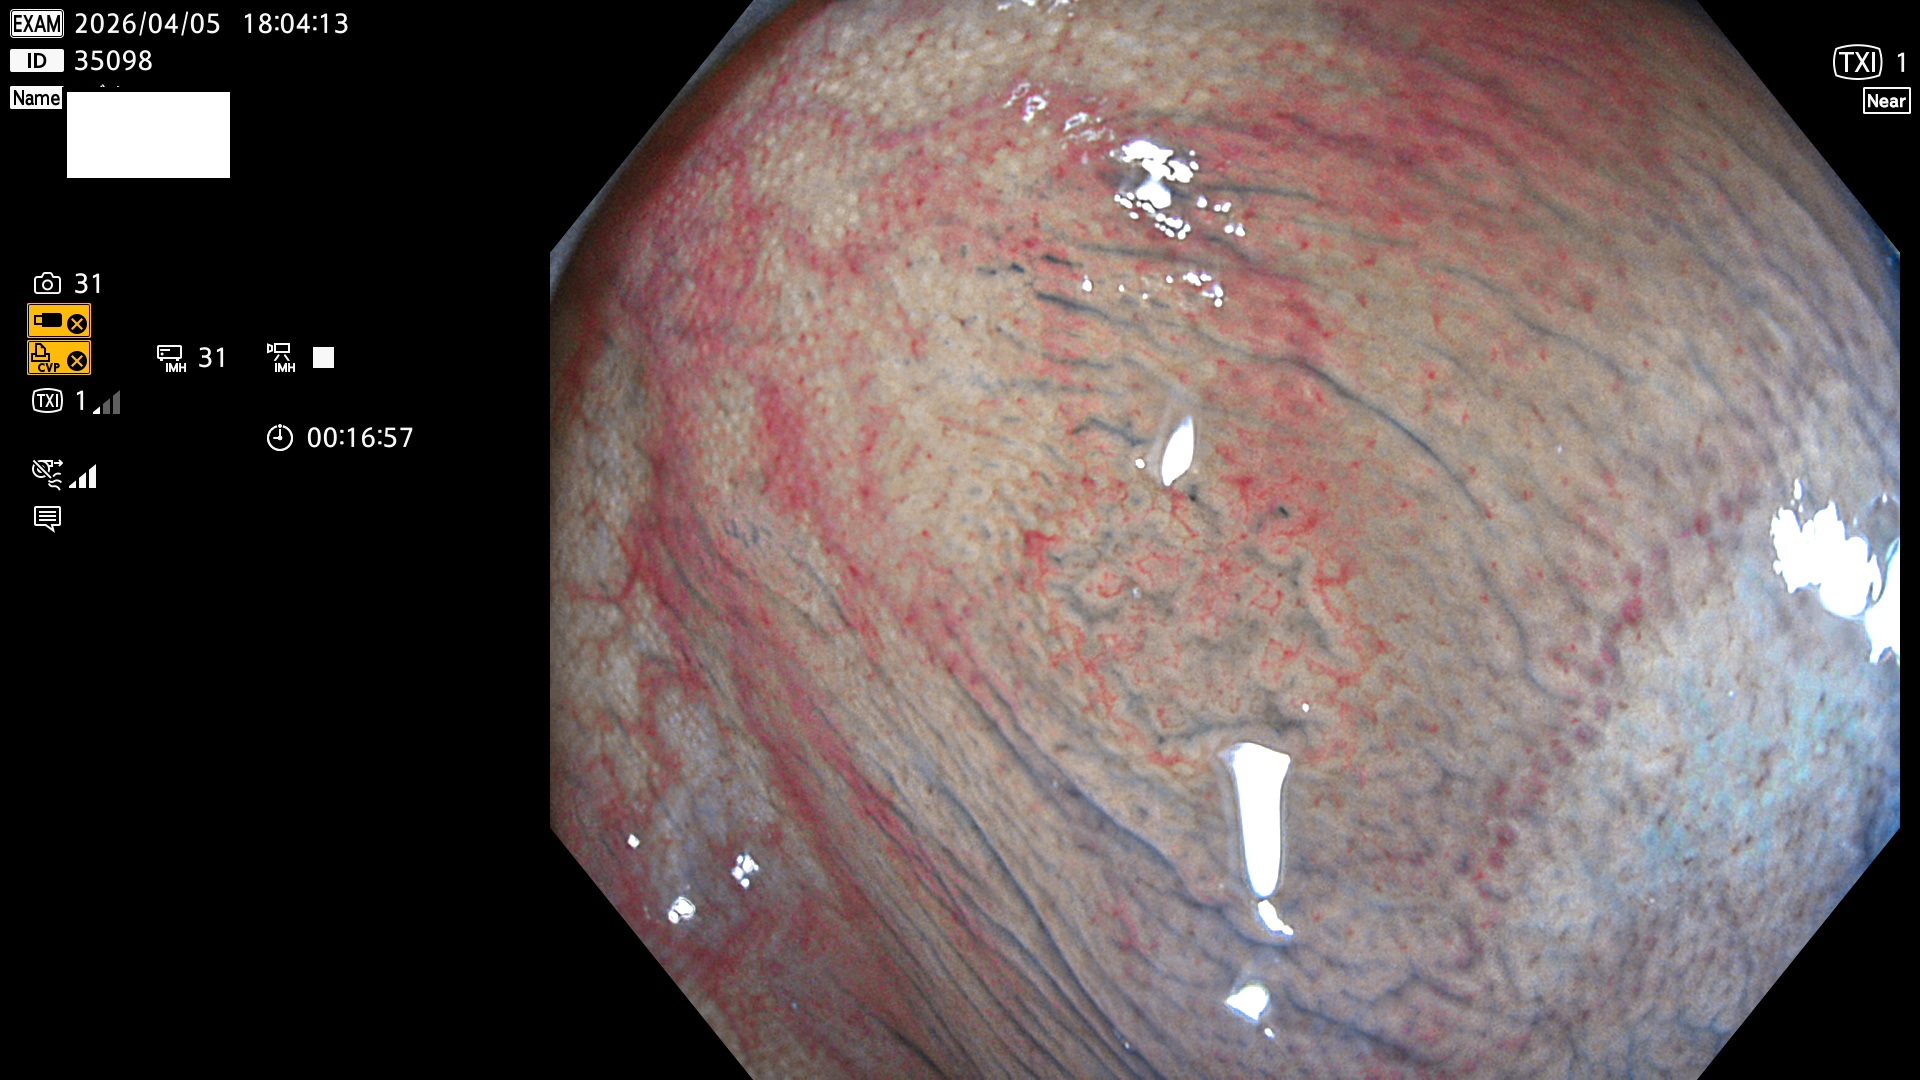

毎週の検査(木・金・土・日)に発見されたUbとUc型・腺腫を、その週の日曜の夜にUPし1週間、提示します。

2026年4月2日〜4月5日の4日間(40件)7個 (Uc_ADR=7個/40人=18%)